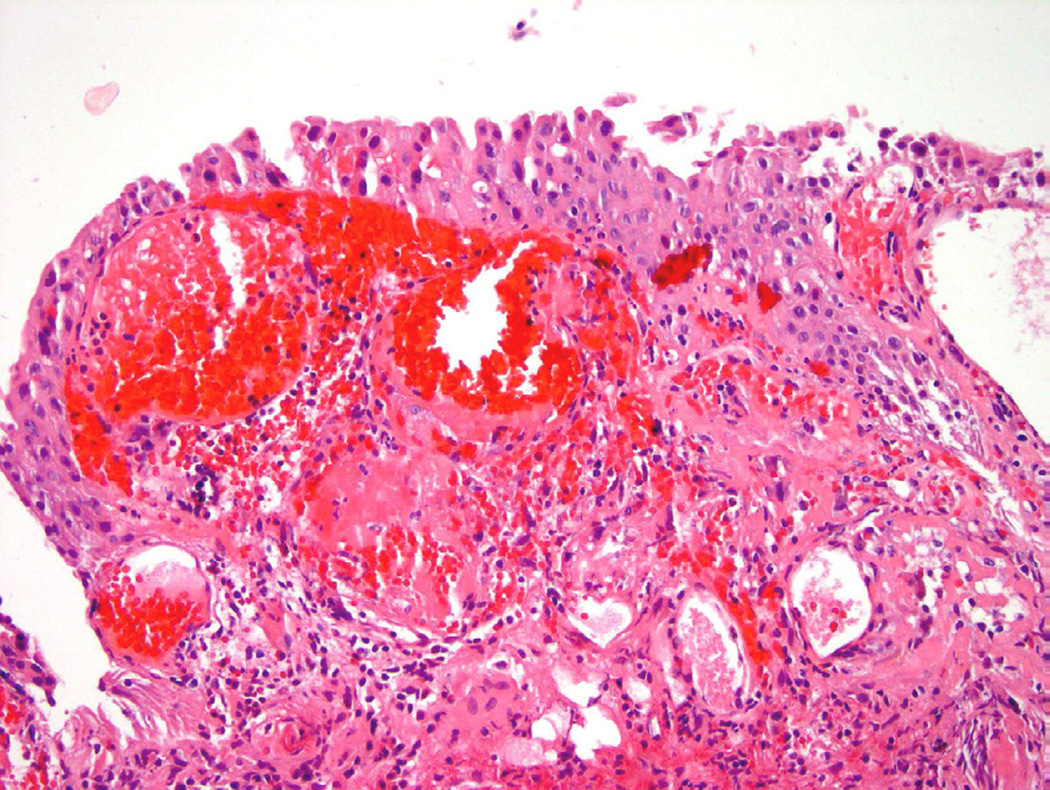

Radiation therapy

Approximately one-fourth of all patients with muscle invasive bladder carcinoma will undergo some form of radiotherapy31. In addition, many patients diagnosed with prostate cancer will also undergo various forms of radiation therapy that can ultimately affect the bladder lining based on its proximity. On cystoscopy, edema, ulceration, and erythema are common findings in addition to areas of mucosal hemorrhage. Histologically, the urothelium shows “radiation atypia”, which includes cellular enlargement, multinucleation, vacuolization, and chromatin clearing (Fig. 14)31. In addition to inflammation and cytologic atypia identified in the epithelium, vascular changes secondary to the radiation include edema, vascular proliferation, vessel wall hyalinization, and thrombosis. Ischemic changes caused by exposure to radiation can lead to long-term sequelae such as mucosal denudation, contractures, and fistula formation32.

Figure 14.

Radiation atypia with a background of inflammation, nuclear atypia and edema.